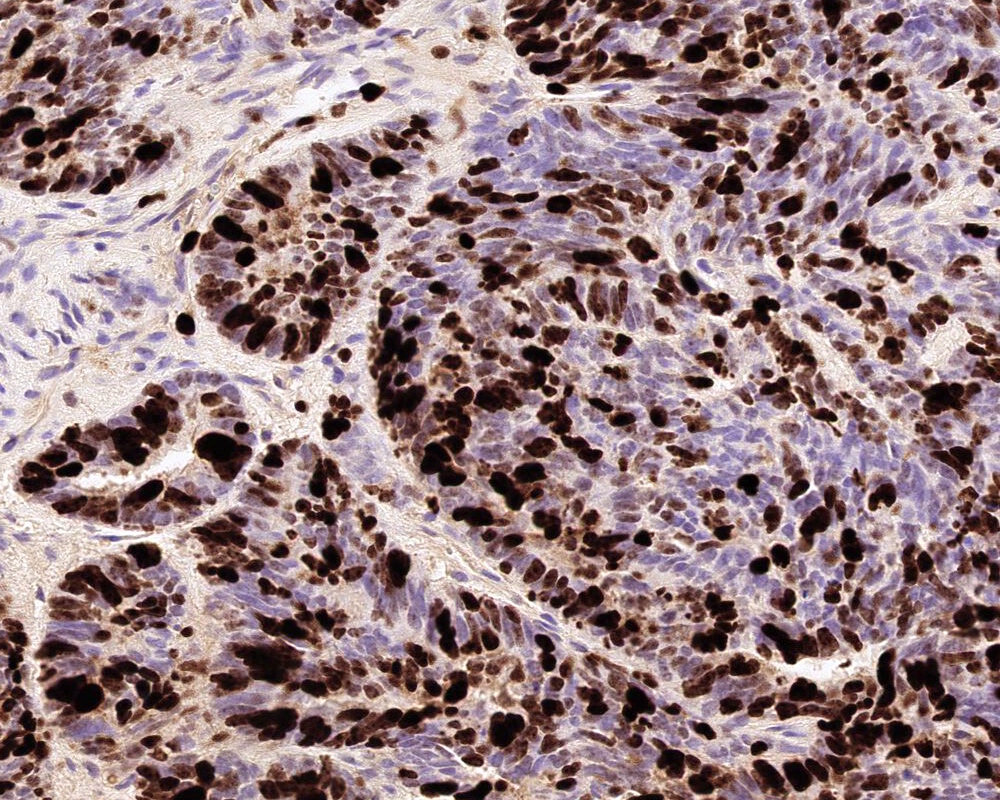

Microscopic (histologic) images

Positive stains

- Transthyretin, KIR7.1, EAAT1, S100, pancytokeratin (cytokeratin, MNF116, AE1 / AE3), CK7 > CK20

- Can be positive for GFAP, synaptophysin, S100

- Ki67 / MIB1 proliferation index may be used for grading (variable and subjective interpretation)

- Choroid plexus carcinoma: p53 variable, SMARCB1 / INI1 and SMARCA4 retained nuclear expression

- References: Neurosurgery 1988;23:384, Acta Neuropathol 1990;80:635, Am J Surg Pathol 2006;30:66, J Neuropathol Exp Neurol 1999;58:398

D. Nuclear INI1 (SMARB1) expression is retained in choroid plexus carcinoma but lost in atypical teratoid / rhabdoid tumor

Choroid plexus carcinomas can mimic other malignant tumors of the childhood, such as CNS embryonal tumors, and it is important to exclude them to guide appropriate treatment. INI1 (SMARCB1) and SMARCA4 immunohistochemistry expression is retained in CPC, which helps to differentiate from aggressive tumor atypical teratoid / rhabdoid tumor (AT / RT). A negative LIN28a differentiates from embryonal tumor with multilayered rosettes (ETMR, bearing C19MC alterations). Diffuse synaptophysin expression with patchy GFAP and presence of Homer-Wright rosettes should raise the possibility of medulloblastoma. Diffuse GFAP expression with possible IDH1 expression (in younger adults) with microvascular endothelial proliferation and necrosis would indicate a high grade glioma / glioblastoma. DNA methylation array and classification of CNS tumors will help in definitive classification. Nevertheless, it is important to have a solid histological diagnosis in case the array fails to confidently classify the tumor.